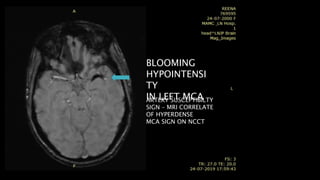

BLOOMING

hypointensity

Large infarcts may show –prominent hypointense

medullary veins

haemoglobin deoxygenation

HYPOINTENSI

TY

IN LEFT MCAARTERY SUSCEPTIBILTY

SIGN – MRI CORRELATE

OF HYPERDENSE

MCA SIGN ON NCCT

• #50 Here is an example of abnormal linear hypointensity noted in left MCA in the axial SWI image consistent with thrombus. This is called artery susceptibility sign which is considered as MRI correlate of hyperdense MCA seen on NCCT

• #51 Here is another example of 47y old male. FLAIR axial images show shows patchy hyperintensity in left caudate nucleus , lateral putamen and parietal cortex. T2* GRE shows several linear hypointensities in the affected MCA branches, consistent with haemoglobin deoxygenation caused by slow stagnating arterial blood flow.